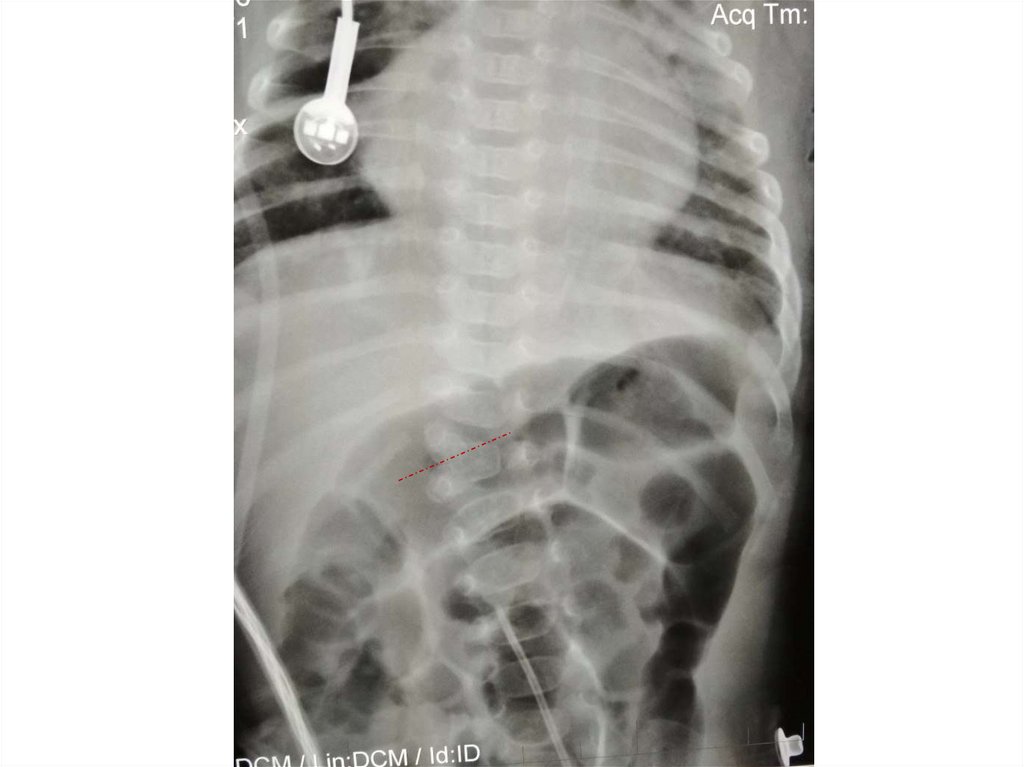

Назовите

• Вид исследования

• Область исследования

• Патологию